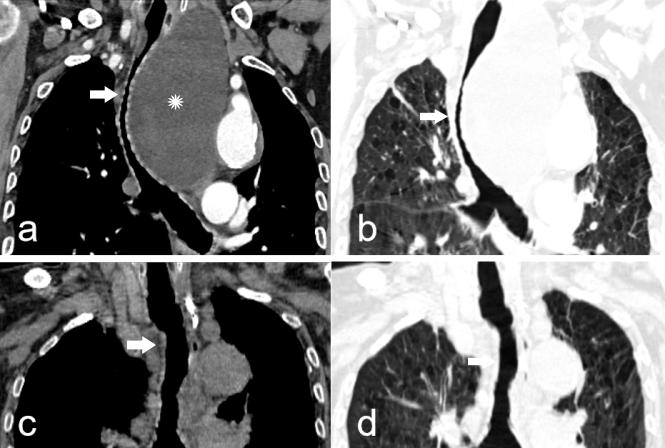

11月3日,患者坐轮椅进入了CT介入手术室,在介入医学中心主任徐晓雪教授的指导下,由介入医学中心副主任李兵副主任医师、余枭漩医师进行手术。在CT精确引导下,穿刺至囊肿内,并放置引流管,引流囊液,随着囊液的引出,患者明显感受到呼吸困难逐步缓解。为了防止囊肿复发,在囊液完全引出后进行了囊肿硬化治疗。术后CT复查显示患者受压气管复位、狭窄解除,管腔宽度恢复。手术全程仅用40分钟,使用局部麻醉,患者生命体征全程监控,手术过程中老人家意识清醒、生命体征平稳。近日老人已顺利出院,呼吸困难及吞咽困难明显缓解,生活质量显著提高,老人家及家属对治疗效果极为满意。

(术前、术后CT对比:术前主支气管明显受压变形、变窄(图a、图b)。术后气管复位,管腔恢复正常(图c、图d)。白色箭头所示为主支气管。)